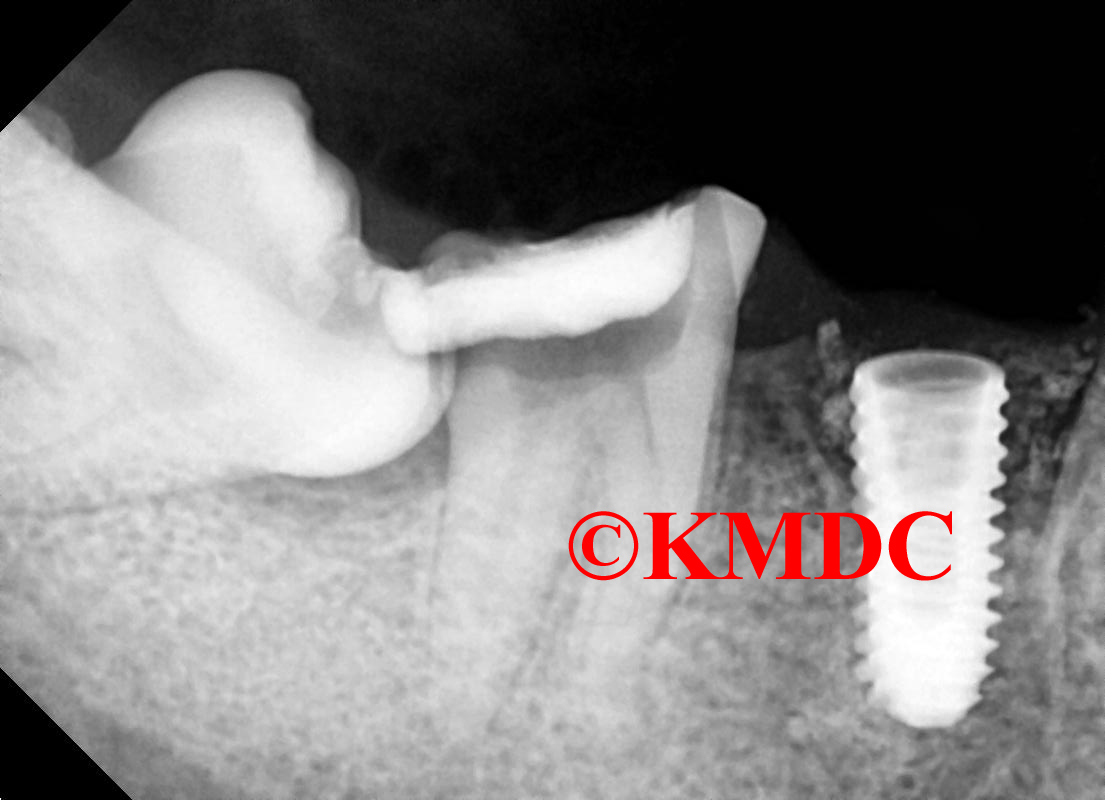

Clinical Gallery